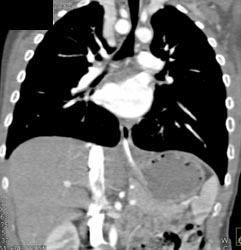

Airway Narrowing Due to Double Arch